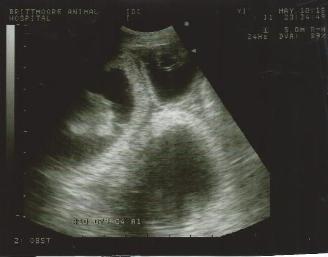

May 10,   2018

It's confirmed....

Creedence and Beau are

expecting a passel of puppies around June

3. 2018.  Stay tuned for updates !!!